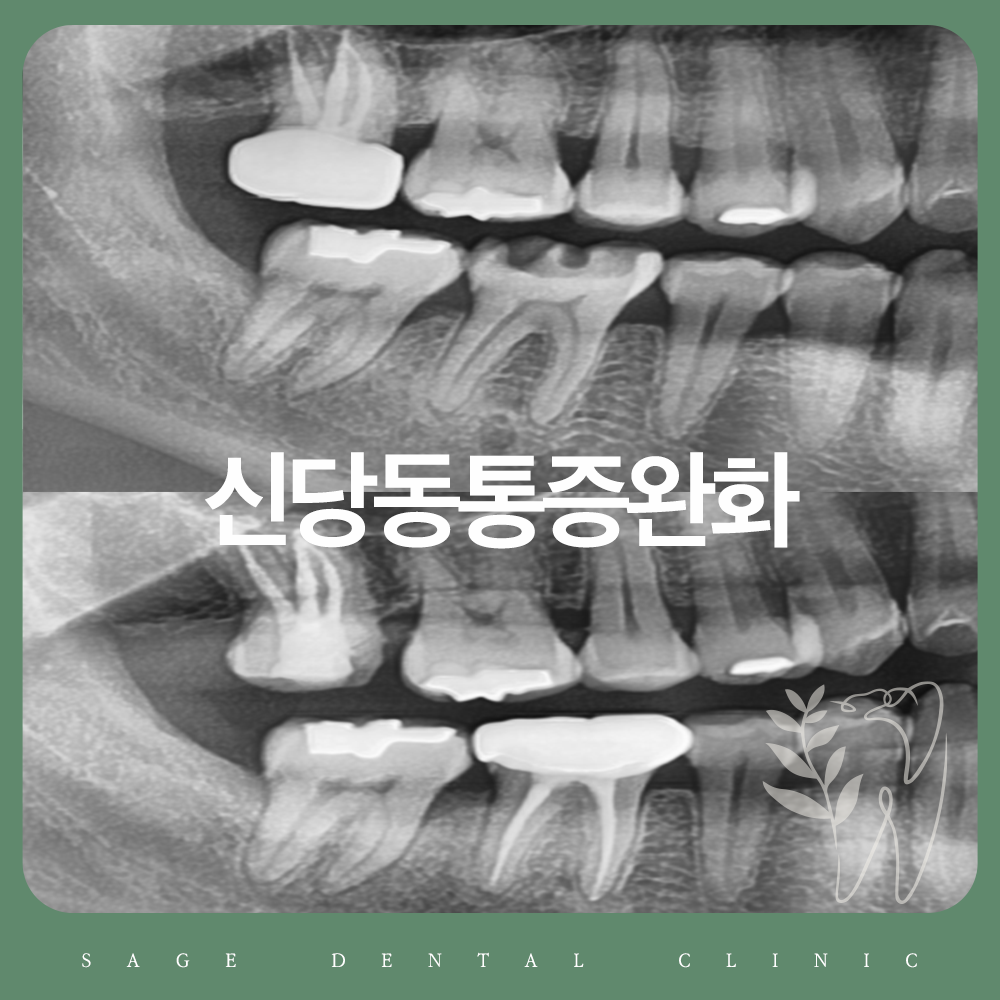

23.05.06(육안상 발견된 균열선)

23.05.06(엑스레이 소견 상 치수침범은 없는 상태)

다행히 엑스레이 소견 상 치아의 신경을 침범하지는 않았고, 치아의 균열선만 육안으로 관찰되는 상태였습니다.